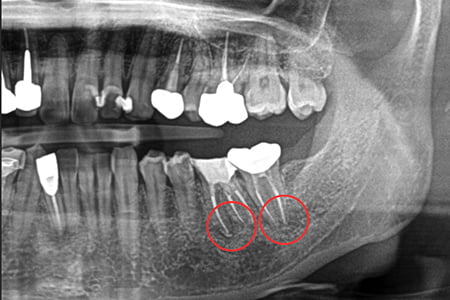

初診・診断

問診・口腔内診査・レントゲン検査で状態を詳しく診断します。

治療例2

| 症状 | 左下奥歯が噛むと違和感がある |

|---|---|

| 治療方針 | 歯根嚢胞を認め歯が保存可能か分析。保存可能であれば根管充填及びファイバーコア、補綴修復を行う |

| 治療期間 | 1年9カ月 |

| 治療費用(税込) | ¥666,600 ※2歯分 |